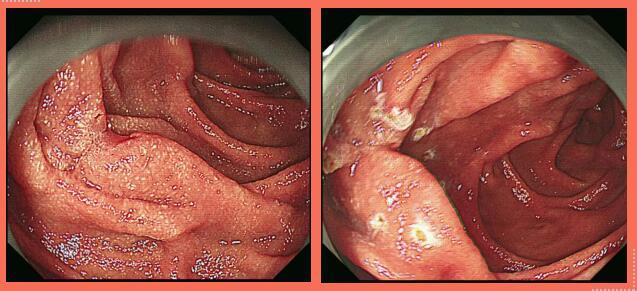

患者刘某因“反复腹痛1月”来潍医附院就诊,进行胃镜检查:慢性萎缩性胃炎、十二指肠降段粘膜病变性质待诊,病理示:管状腺瘤,局灶腺体呈高级别上皮内瘤变。遂以“十二指肠原位癌”收入医院消化内二科。

该患者肿瘤位于十二指肠降段后壁,平十二指肠乳头旁约2.0cm,该处肠管与胰头连接紧密,前方覆盖横结肠、大网膜、胆囊,若按照传统ESD手术剥离病变,穿孔风险极大,且不易内镜下封闭创面。而腹腔镜手术无法准确定位病变位置及范围。传统的外科手术不仅切口长、且创伤大,恢复慢,患者术后痛苦重。